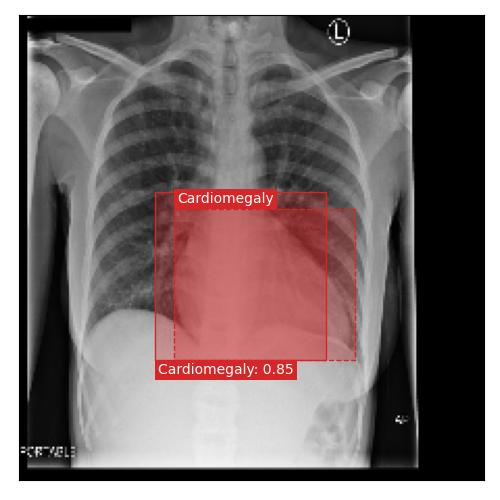

Qualitative Results

As shown in Fig. 4 Loc-ADPD detects cardiomegaly almost perfectly, as it is always exactly localized at one anatomical region. Other pathologies are detected but often with too large or too small boxes as they only cover parts of anatomical regions or stretch over several of them, which cannot be completely corrected using WBF. Detection also works well for predicting several overlapping pathologies. For qualitative comparisons between Loc-ADPD and MIL-ADPD, we refer to Appendix 0.B.